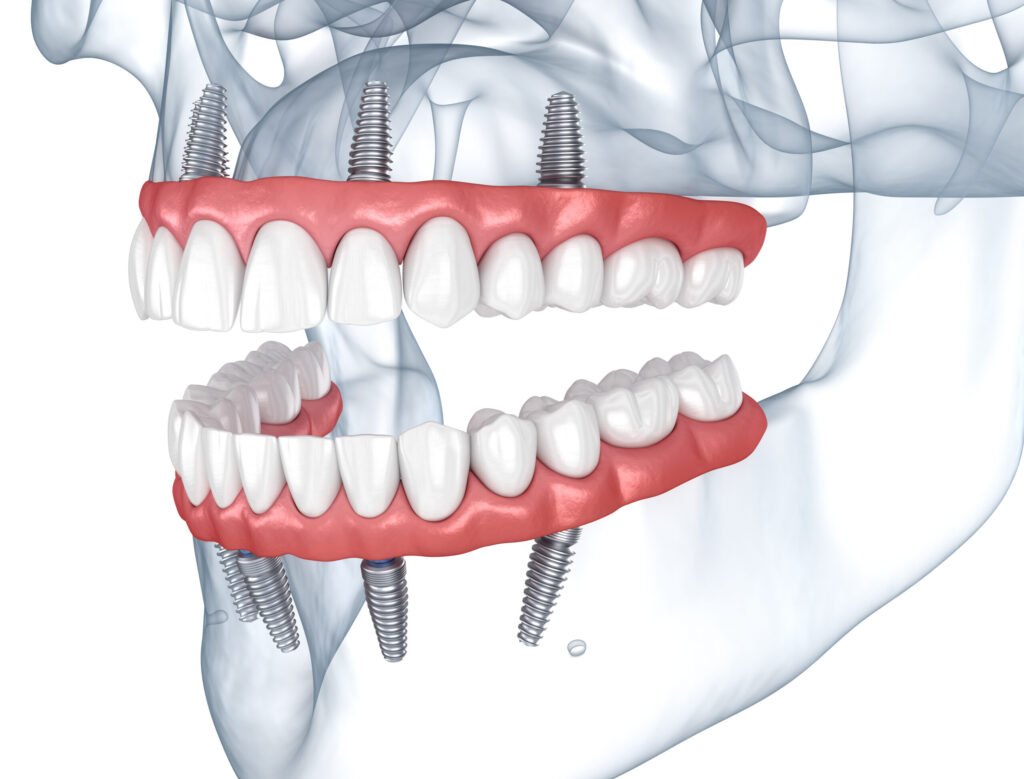

Moderne Computersimulationen helfen uns, die Implantate perfekt zu platzieren, während unser Zahntechniker-Team den Zahnersatz digital designt und ein präzises Modell Ihres Kiefers erstellt. Dieses dient als Grundlage für die Implantation, bei der die Implantate in den vorbereiteten Bereichen eingesetzt werden – häufig so stabil, dass sie noch am selben Tag belastet werden können. Für festen Halt setzen wir pro Kiefer in der Regel vier bis sechs Implantate ein. Zwei davon werden im vorderen Bereich und zwei im hinteren Bereich in einem speziellen 30-Grad-Winkel verankert. Das sorgt für maximale Stabilität und eine sichere Basis für Ihre neuen Zähne. Auch bei kleineren Zahnlücken wird präzise und effizient gearbeitet. In enger Zusammenarbeit zwischen unseren Zahnärzten und Zahntechnikern entstehen passgenaue Lösungen – selbst bei komplexen Behandlungen, und das alles an nur einem Tag. Vertrauen Sie auf unsere Expertise und freuen Sie sich auf feste Zähne, die Ihnen ein unbeschwertes Lächeln und Lebensqualität zurückgeben – schnell, sicher und komfortabel.

Bei klassischen Implantaten sind im Oberkiefer mindestens 8 und im Unterkiefer 6 Implantate erforderlich, um eine Implantatbrücke sicher zu verankern, wenn keine eigenen Zähne mehr vorhanden sind.

Für eine stabile Verankerung ist ausreichend Kieferknochen in Höhe und Breite erforderlich. Fehlt dieser, muss der Kiefer zunächst mit Knochenersatzmaterial aufgebaut werden, bevor die Implantate eingesetzt werden können.

Dank der modernen All-on-4-Technologie hat sich dies jedoch erheblich verändert. Mit dieser Methode sind im Ober- und Unterkiefer nur 4 bis 6 Implantate notwendig, um feste Dritte Zähne sicher zu befestigen. Durch die spezielle Konstruktion und das angewinkelte Einsetzen der Implantate wird weniger Kieferknochen benötigt, was eine stabile Verankerung auch bei eingeschränkten Knochenverhältnissen ermöglicht.

Ein besonderer Vorteil dieser Technik: Die Implantate können sofort belastet werden, sodass der Patient noch am selben Tag einen provisorischen, festen Zahnersatz erhält. Zudem führt die kürzere Behandlungsdauer zu deutlich niedrigeren Kosten im Vergleich zu traditionellen Implantaten.